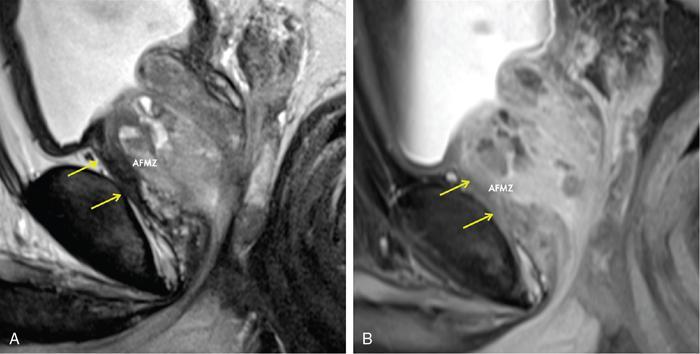

Karthik Ganesan, Disha Lokhandwala, Ujjwal Bhure, Jay Mehta Morphogenesis of the male genitourinary system is governed by the coherent interaction of three units, namely the Wolffian duct, urogenital sinus and foetal gonads. The Wolffian ducts are the embryonic precursors of the male internal genitalia, arising in the anterior intermediate mesoderm at 4 weeks of gestation. They elongate as a cord of cells that caudally extend to the urogenital sinus. Between 5 and 8 weeks of gestation, the urorectal septum divides the cloaca into a ventral compartment, which forms the urogenital sinus, and a dorsal compartment, which forms the rectum. The gonads form as epithelial thickenings on the ventromedial surface of the mesonephros and produce testosterone at 8 weeks of gestation, reaching a peak at 10–15 weeks. Under the effect of testosterone produced by the foetal testis, the prostate anlage forms at the tenth week of gestation. Precursor of the anlage begins with proliferation of solid epithelial buds from the epithelium of the urogenital septum into the adjoining mesenchyme in response to interaction of 5α-dihydrotestosterone with mesenchymal androgen receptors. As growth progresses, solid cords of epithelial cells are formed, growing into the mesenchyme in a specific three-dimensional arrangement (establishes the lobar divisions of the prostate gland). These solid cords develop a central lumen at birth and are lined by a layer of flat basal epithelium and a luminal layer of tall columnar secretory epithelium. Mesenchymal component forms the stroma, which has a large proportion of smooth muscle. Postnatally, the epithelial cords continue to arborize till puberty without any change in volume or glandular architecture. Although the foetal prostate has been described to have a histologically distinct peripheral zone (PZ) as early as 12 weeks of gestation, the mature zonal anatomy develops in concordance with the androgen surge at puberty. The most commonly utilized ultrasonographic technique for the evaluation of the prostate is via a suprapubic approach. The abdominal transducers used in this approach are relatively low frequency and while it offers the advantage of greater depth of penetration without intracavitary probe insertion; however, it does not depict the zonal anatomy and its chief application lies in volume estimation. Hence, transrectal ultrasonography (TRUS) completely outweighs the transabdominal approach in terms of depicting zonal anatomy, visualizing and localizing small lesions, demonstrating vascularity and performing biopsies. TRUS is performed using high frequency transducers (5–7.5 MHz) to optimize soft tissue resolution. An enema is administered 1 h prior to the examination to clear the field of insonation. Patient is positioned in left lateral decubitus, with knees bent toward the chest and ideally a digital rectal examination (DRE) is conducted prior to probe insertion. The transducer is first draped with a sterile barrier and lubricated, After insertion, the barrier is filled with 40–50 cc of water, making sure that no air enters. On completion, water is aspirated and the probe is withdrawn. The gland is initially scanned in the axial plane from the base to the apex, beginning at the level of the seminal vesicles, and the probe is gradually withdrawn to view the entire glandular parenchyma in axial sections up to its caudal aspect. This approach allows a cursory evaluation of glandular symmetry as both halves of the prostate can be evaluated simultaneously. Subsequently, sagittal views are acquired by rotating the probe across the transverse span of the gland, demonstrating the seminal vesicles, midline gland (visualizing both the apex and the base), with sequential scanning up to the contralateral margin of the gland. Sonographically, the prostatic capsule is seen as a smooth well-delineated, hyperechoic structure. With the newer ultrasound systems, the zonal anatomy can be delineated by TRUS; PZ appears echogenic relative to the central zone (CZ) and the transition zone (TZ), which are hypoechoic in juxtaposition (Fig. 11.12.1). Anterolaterally, the preprostatic venous plexuses are seen as anechoic tubular structures with intervening echogenic preprostatic fatty tissue. Glandular volume is estimated using an ellipsoid formula by obtaining the maximum anteroposterior, superoinferior and transverse dimensions and multiplying their product by π/6. Colour Doppler imaging is utilized to illustrate vascularity, as majority of the normal prostatic tissue (excluding the neurovascular bundles [NVBs] and pericapsular and periurethral regions) has symmetrical but sparse flow and an increased microvessel density raises the suspicion of prostatic carcinoma. However, the appearances of prostatic carcinoma can be variable on colour Doppler imaging, ranging from focal increase in vascularity around a nodule to an asymmetric increase in size and number of vessels on the affected side and conventional Doppler has found to elevate specificity by about 5%–10%. Additionally, Doppler imaging has also demonstrated some utility in distinguishing fibrotic tissue from local recurrence. However, vessels supplying cancerous tissue are of the order of 10–50 μm, which is well below the 1-mm resolution limit of conventional Doppler techniques. Contrast-enhanced colour Doppler imaging overcomes this limitation and facilitates imaging of microvessels, using intravenously administered microbubbles (less than 10 μm diameter) of an inert gas (sulphur hexafluoride) with a lipid or galactose shell, allowing quantification of blood flow in the cancerous microvessels. Additionally, these microbubbles act as vascular tracers and by monitoring the passage of a bolus injection through the tissue of interest, time–intensity curves are created. This permits the formulation of functional indices, including bolus arrival time, time to peak intensity, area under the curve and wash-in/wash-out curves. These indices can further extrapolate functional images, on a pixel-by-pixel basis, overlaid on grey-scale images. Quantitative methods to demonstrate perfusion are based on the destruction of microbubbles by high-power ultrasound pulses, and then observing the rate of microbubble replenishment in the field of interest to calculate flow rate. Halpern et al. utilized contrast-enhanced ultrasound and intermittent harmonic imaging with power Doppler, and exhibited an increment in sensitivity from 38% to 65% with a specificity of 80% in prostate cancer detection. Cadence contrast pulse sequencing (CPS) is a low-power multipulse imaging technique utilizing pulses with variable amplitudes and phases followed by a summation of the resulting echoes, permitting tissue suppression, allowing detection of even a small amount of contrast agents retained in the tissues. Real time elastosonography evaluates and quantifies tissue stiffness (Young’s modulus) by measuring strain under an applied stress (transducer compression) and maps areas of variable stiffness in colour-coded and grey-scale images simultaneously and shows potential in improving prostatic carcinoma detection. In a study comparing elastography and T2-weighted (T2-w) endorectal magnetic resonance imaging (MRI), similar sensitivity rates and negative predictive values (NPVs) were attained in the detection of prostatic carcinoma. Prostate gland is an inverted cone-shaped subperitoneal retropubic gland, with its base located rostrally and apex located caudally. The base is attached to the bladder neck and the apex sits on the urogenital diaphragm and abuts the medial surface of the levator ani muscles, namely the pubourethralis portion, which is separated from the inferolateral surfaces of the gland on either side by the prostatic venous plexus. Normal prostate gland measures approximately 4 × 3 × 3 cm, 15–20 g in weight, with a median volume of 11.5 mL (range, 1.6–20.6) in patients between 21 and 25 years and a median volume of 39.6 mL (range, 13–169.8) in patients between 38 and 83 years. The first comprehensive publication describing the anatomical subdivision of the prostate gland was in 1912 by Lowsley, based entirely on the embryonic glandular morphology at a series of gestational age groups. The budding prostatic ducts were seen to proliferate in five distinct clusters from the primitive urogenital sinus, which formed the basis of its lobar subdivision. It was divided into a ventral lobe (anterior to the urethra), two lateral lobes (lateral to the ejaculatory ducts), a posterior lobe (between the ejaculatory ducts) and a middle lobe (above the ejaculatory ducts). This classification had several shortcomings, the foremost being inclusion of only the embryonic prostate during its conception. Frank highlighted these aspects in 1953 and stated that no definite lobar boundaries exist in the adult prostate and further criticized the exclusion of periurethral glands (inner gland), identifying them as the sole site of origin of benign prostatic hyperplasia (BPH). The chief drawback of all research prior to 1968 was the lack of a concrete histological basis to support the seemingly arbitrary subdivision. McNeal was the first to ascertain histological heterogeneity within the glandular tissue and used it as the basis of his well-acclaimed prostatic zonal classification. The zonal anatomy of the prostate gland conceived by McNeal divided the gland into four distinct zones, namely the TZ, PZ, anterior fibromuscular zone (AFMZ) and the CZ (Fig. 11.12.2). McNeal used the plane of the distal urethra to describe the zonal relationships and divide the gland broadly into three parts, namely the base, midgland and the apex (Fig. 11.12.3). The improved understanding of the prostate anatomy coincided with the development of MRI in the late 1980s, which could depict the zonal anatomy, unlike ultrasonography (USG) or computed tomography (CT). Patterns of ductal growth and radiation from the prostatic urethra form the basis of the zonal anatomy of the gland. Ducts arising from the proximal urethral segment grow towards the urinary bladder. Tiny ducts which are confined by the preprostatic sphincter form the small periurethral gland, whereas ducts which develop distal to the lower border of the preprostatic sphincter extend laterally and then anteromedially to form the TZ. Ducts arising from the verumontanum in the vicinity of the ejaculatory duct orifices and are directed towards the base along the course of the ejaculatory ducts form the CZ, whereas ducts which arise from the lateral recess of the posterior urethral wall of the verumontanum and distal urethra radiate laterally to form the PZ and rostrally posterior to the CZ at the base of the gland. PZ is the dominant glandular component of the prostate gland comprising approximately 70% of the glandular tissue. On T2-w images, the normal PZ has a high T2 signal intensity (SI), owing to the abundant ductal and acinar elements with sparsely interwoven smooth muscle, and can broadly divided into three sections as per the sector map in Prostate Imaging Reporting and Data System Version 2.1 (PI-RADS v2.1), namely posterior medial, posterior lateral and anterior sections (Fig. 11.12.4). At the apex, the anterior sections have a horn-like morphology, curving anteromedially, to nearly encircle the urethra and abut the AFMZ. At the midgland level, the PZ comprises the posterior, both lateral and the anterolateral parts of the gland. At the base, the PZ is located posterior and superior to the CZ and TZ. CZ is an ovoid-shaped structure at the base of the gland, comprising approximately 25% of the glandular tissue, with its apex located at the verumontanum, surrounding the ejaculatory ducts. Beyond age 35, volume of the CZ starts to gradually diminish, as well as the CZ is compressed by the enlarged TZ. In the initial MR studies of prostate, the CZ could not be easily delineated from the TZ. Vargas et al. demonstrated in a population with a mean age of 60 years undergoing MR for prostate cancer assessment, the CZ was visible in 81%–84% of patients. Hansford et al. identified the CZ in 92%–93% of patients on T2-w images and 78%–88% of patients on apparent diffusion coefficient (ADC) maps. Histologically, substantial differences exist between the CZ and PZ, which reflect in the differential appearance on T2-w imaging. These differences are probably attributable to the differential origin, as the CZ is derived from the Wolffian duct, and the PZ and TZ are derived from the urogenital sinus. In the CZ, the acini appear larger and more irregular, with numerous epithelial covered ridges or septa project from the walls of the acini into the lumen, forming a characteristic Roman bridge architecture and intraglandular lacuna, with a prominent basal layer, crowded epithelial cells with granular eosinophilic cytoplasm, decreased luminal fluid and compact stroma. PI-RADS v2 has discouraged the use of the term central gland, as it is not reflective of zonal anatomy or reported on pathologic specimens. CZ demonstrates homogeneously low signal on the T2-w images and ADC maps and can, therefore, mimic prostate cancers. CZ is best identified on the coronal plane T2-w images paralleling the plane of the distal urethra, and appears as a symmetric paramedic paired structures surrounding the ejaculatory ducts from the base of the gland to the verumontanum (Fig. 11.12.5). TZ comprises approximately 5% of the glandular tissue of the prostate. On T2-w images, the TZ normally appears as a homogeneously hypointense structure surrounding the proximal urethra at the base and the midgland level; however, it can also demonstrate inconsistent SI, depending on the relative proportion of glandular and stromal elements (Fig. 11.12.6). Glandular hyperplasia produces higher SI (dominance of acinar elements and secretions), while stromal hyperplasia exhibits lower SI (dominance of muscular and fibrous elements). The TZ is easily demarcated from the PZ by a thick homogeneously low T2 signal surgical capsule, which becomes pronounced in BPH. With increasing age, the TZ demonstrates variegated signal on the T2-w images and ADC maps, due to differential growth of the stromal and glandular elements. AFMZ is a nonglandular muscular tissue that drapes the anterior surface of the gland, superiorly blending into the smooth muscles of the bladder neck and inferiorly extending to the prostatic urethra at the glandular apex. AFMZ is comprised of smooth muscles, which blends with the smooth muscle fibres surrounding the urethra, and rostrally merges with the bladder neck and preprostatic sphincter. High smooth muscle content of the AFMZ is responsible for the MR signature, where in it appears markedly hypointense on the T2-w images and ADC maps, and hypoenhances on the multiphase contrast series (Fig. 11.12.7). With the advancing age, temporal reduction in the size of the AFMZ is noted due to the compressive effects of the BPH. Capsule surrounds the prostate gland, anteriorly merging with the AFMZ anteriorly. Two discrete defects are identified in the prostate capsule, at the base of gland where the ejaculatory ducts enter the prostate and at the apex where in the stroma blends with the sphincter. The capsule is perforated along the anterolateral aspect by multiple vessels and nerves. The capsule appears as a thin dark rim surrounding the gland on the T2-w images and may reveal delayed enhancement on the postcontrast images (Fig. 11.12.8). Primary goal of radical prostatectomy (RP) is to achieve oncologic efficacy, both in terms of short-term and long-term clinical outcomes. However, as the majority of prostate cancers have an indolent clinical course, preservation of function in terms of continence and potency is equally important, and the key to this is a keen understanding of the fascial anatomy and neuroanatomy of the prostate gland. Fascial anatomy of the prostate gland is anatomically complex and poorly understood, and a thorough understanding of the interfacial planes is crucial to avoid mechanical or thermal injury to the NVBs. Periprostatic fascia comprises of a condensation of layers of connective tissue that encapsulate the gland and suspend it from anterior pelvic wall via puboprostatic ligaments. Laterally, the visceral and parietal endopelvic fascial layers fuse to form the fascial tendinous arch. Periprostatic fascia covers the prostate gland and capsule, comprises of two fascial layers, including an inner layer (prostatic fascia) and an outer layer (levator ani fascia), with thin interfascial planes separating these fascia from one another and the prostate capsule. Posteriorly, a continuous fascial layer known as Denonvilliers’ fascia covers the prostate and seminal vesicles. Distribution of periprostatic nerves is highly variable, with growing evidence of nerves both along the dorsolateral and ventrolateral surfaces of the prostate gland. Most of the periprostatic nerves are found posterolaterally; however, a significant portion of the nerves are located ventrally as seen by Eichelberg et al. (21.5%–28.5%) and Lee et al. (19.9%–22.8%). Although anatomic studies have confirmed the presence of ventrolateral periprostatic nerves, the exact clinical importance and functionality of these nerve fibres has not been proven. The cavernous nerves are situated posterolaterally and are the basis of nerve-sparing RP procedure proposed by Walsh and Donker. Unlike the initial theory of Walsh and Donker, few papers have proposed that the nerves are diffusely scattered along the surface of the gland in the form of a curtain or spray-like arrangement without clear bundle formation. Kourambas et al. assessed the precise relationship of the NVBs and cavernous nerves to Denonvilliers’ fascia and proposed that the nerves were not restricted posterolaterally, but were rather diffusely scattered within the fascia extending up to the midline (Lunacek et al., Takenaka et al.). On the basis of more diffuse arrangement of the periprostatic nerves, surgical techniques have been modified, resulting in a more anterior dissection called the ‘curtain dissection technique’ or alternatively a ‘superveil’ technique to preserve the NVBs within the lateral prostatic fascia. The NVB lies within areolar connective tissue surrounding the gland, which separates the capsule from the periprostatic fascia and provides a plane of dissection during nerve-sparing prostatectomy. Prostate gland is supplied and drained by periprostatic vessels, which also supply and drain the penis. Arterial supply of the gland is highly variable and is typically from branches of the internal pudendal artery, which course inferior to the gland prior to supplying the penile cavernosal tissue. Off late, these vessels have gained prominence in radiation-induced erectile dysfunction (ED) (potential vasculopathy), which have led to the development of newer vessel-sparing radiotherapy techniques. Further, with the advent of prostate arterial embolization in benign prostatic hypertrophy (BPH), the vascular supply of the gland is becoming increasingly vital to understand. Gland drains into the obturator, internal iliac, external iliac, common iliac and presacral lymph nodes. Dorsal venous complex is identified immediately ventral to the gland and also drains the penis. Periprostatic nodes are uncommon, are usually discovered near the base of the gland, and are only occasionally seen on MRI. Urethra is the principal anatomic reference point in the prostate gland. Urethra can be divided into a proximal segment and a distal segment, the point of differentiation being located at the verumontanum wherein the urethra makes an approximately 35-degree angulation. The angulation is highly variable and is further affected by the growth of the TZ. On MRI, the distal segment is more conspicuous vis-à-vis the proximal segment and appears a hyperintense core surrounded by a low signal rim on T2-w images. Preprostatic sphincter encases the proximal urethra from the base of the gland to the base of the verumontanum and merges with the AFMZ anteriorly. Verumontanum appears hyperintense on the T2-w images, lies within the distal urethral segment, beyond which the distal urethral segment is partially encircled by striated muscles which blend with the external sphincter beyond the apex of the gland. External sphincter is located distal to the apex is incomplete posteriorly and is anchored into the PZ and surrounds the membranous urethra. Damage to the external sphincter during RP or transurethral resection of the prostate (TURP) may lead to urinary incontinence. Seminal vesicles are paired structures identified posterosuperior to the base of the prostate gland, which appear as convoluted fluid-filled structures. Due to the high fluid content within the normal seminal vesicles, these structures appear as paired structures with intermediate signal walls surrounding a hyperintense core on T2-w images (Fig. 11.12.9). Vas deferens are paired structures located rostral to the base of the gland and anteromedial to the seminal vesicles and appear as cord-like structures with variable signal on the T2-w images. Duct of the seminal vesicle and vas deferens unite in the posterior aspect of the base of the gland to form the ejaculatory duct, which courses caudally to the verumontanum along the plane of the distal urethra, and drain into the orifices in the midconvexity of the verumontanum. Prostate-specific antigen (PSA) is a serine protease, secreted by epithelial cells of the prostate gland and has been found in normal, benign and malignant prostatic tissues. Traces of PSA have also been isolated from endometrial tissue, breast tissue, adrenal neoplasms and renal cell carcinomas; however, for all clinical purposes, PSA is considered as an organ-specific biomarker. Papsidero first demonstrated and quantified serum PSA, which steered the epoch of prostate cancer screening and early detection of prostatic carcinoma. Subsequent studies showed that PSA screening often led to overdiagnosis of low-grade prostate cancers, with no survival difference between the PSA screened and nonscreened groups. Additionally, PSA levels were found to be elevated in a spectrum of prostatic pathologies apart from carcinoma, including prostatitis and benign hyperplasia. The likelihood of overdiagnosis coupled with the lack of specificity set grounds for the longstanding PSA controversy. Did the benefits of screening outweigh the risks of overtreatment? To elevate the specificity of serum PSA testing, a plethora of indices were devised, including free PSA and total PSA, free-to-total PSA (f/t PSA) ratio, age-specific PSA, PSA velocity (PSA-V) and PSA density (PSAD). Serum PSA exists in three forms; the major form (approximately 75%) is bound to alpha-1-antichymotrypsin, followed by free PSA (constituting 5%–50% of serum PSA). The third form (PSA bound to alpha-2-macroglobulin) is not clinically relevant and cannot be detected by any commercial test. A study by Stenman et al. established that a higher proportion of bound PSA and hence a lower ratio of f/t PSA is associated with prostate cancer. Conversely, free PSA can be utilized during follow-up for men with an initial negative biopsy result, wherein declining free PSA with a persistently elevated total PSA would raise suspicion of a neoplastic aetiology. As per the ACS guidelines (Table 11.12.1) for early detection of prostate cancer, men with a 10-year life expectancy or higher should have the opportunity to make an informed (regarding benefits, risks and uncertainties associated with PSA screening) decision for serum PSA testing, with or without DRE. For those who choose to undergo PSA screening, subsequent screening interval is determined on the basis of baseline PSA value. For values below 2.5 ng/mL, screening interval can be extended to 2 years and for PSA between 2.5 ng/mL and 4 ng/mL, an individualized approach is adopted following risk assessment to recommend either further referral or screening on a yearly basis. A PSA level of 4 ng/mL or higher warrants referral for further evaluation or biopsy, for men at average risk for prostate cancer. Although age-specific PSA (Table 11.12.2) is not a component of the ACS guidelines, it is considered as a beneficial parameter in determining the need for biopsy. As there is an expected rise in PSA values with age, setting a lower cut-off value for younger men would increase the sensitivity of detecting organ confined cancers and a higher value in older men would increase specificity. aThere is no proven rationale for using a single PSA-V threshold value. PSA screening guidelines for treated localized prostate cancers are variable and the definition of biochemical (PSA) recurrence remains debatable. Due to this inconsistency, the Prostate Cancer Guidelines Update Panel recommended a standard definition for biochemical recurrence (BCR) after RP and set a cut-off serum PSA (acquired between 6 weeks and 3 months of surgery) of 0.2 ng/mL or greater, along with a second confirmatory PSA. While there is a significant fall in PSA values after RP and a single raised PSA is sufficient to raise suspicion of recurrence, postradiotherapy recurrence requires a rising trend rather than a single cut-off value. The ASTRO Consensus Panel defined postradiotherapy prostate cancer recurrence as three consecutive raises in PSA values after a baseline has been reached. A hiatus in this definition was that no specific time interval between consecutive increases in PSA was determined. In addition to its utility as a screening tool, PSA is also a good prognosticator when used in conjunction with biopsy Gleason score and clinical T-stage, and several pretreatment prostate cancer risk stratification systems are based on these indices. D’Amico et al. proposed a three-group risk stratification system in 1998, which categorized nonmetastatic (M0) carcinomas as low risk, intermediate risk and high risk. Low-risk prostate cancer was defined as 1992 AJCC T1/T2a, PSA ≤10 ng/mL and Gleason score ≤6. Intermediate-risk prostate cancer was defined as 1992 AJCC T2b, and/or PSA 10–20 ng/mL and/or Gleason 7 disease. High-risk disease included any one of the following: 1992 AJCC ≥T2c, PSA >20 ng/mL or Gleason 8–10 disease. In 2001, the GUROC published the results of a consensus meeting which categorized the groups as follows: low risk – 1997 AJCC T1–T2a, PSA ≤10 ng/mL and Gleason ≤6; intermediate risk – 1997 AJCC T1–T2, PSA ≤20 ng/mL and Gleason ≤7 not otherwise low risk and high risk – 1997 AJCC T3–T4 or PSA >20 ng/mL or Gleason 8–10. In due course, newer classification systems have been developed (Table 11.12.3), including the National Comprehensive Cancer Network (NCCN, USA), National Institute for Health and Clinical Excellence (NICE, UK), European Society of Medical Oncology (ESMO), American Urological Association (AUA) and the European Association of Urology (EAU). The NCCN guidelines also incorporate very low-risk (T1c, and Gleason score ≤6, PSA ≤10 ng/mL, <3 positive biopsy cores each ≤50% involved and PSAD of <0.15 ng/mL/g) and very high-risk (T3b–T4) categories. AUA, American Urological Association; EAU, European Association of Urology; GUROC, Genitourinary Radiation Oncologists of Canada; NICE, National Institute for Health and Clinical Excellence; CAPSURE, Cancer of the Prostate Strategic Urologic Research Endeavour; NCCN, National Comprehensive Cancer Network; ESMO, European Association of Urology; T, T-stage; GS, Gleason score; PSA, prostate-specific antigen. Note: Use of the 1997 TNM staging system (T2a one lobe involvement, T2b two lobes involvement, no T2c category). PSA, DRE and TRUS form the diagnostic triad for prostatic carcinoma. It has been well established that manipulations of the prostate gland, including prostatic massage, cystoscopy and perineal biopsy cause a potential increase in serum PSA levels. This raised the question of TRUS affecting PSA levels and it was found to cause a very small rise in PSA only in patients with prostatitis. The effect of DRE on serum PSA levels is also controversial, while some studies found a transient increase in PSA, others found no significant rise in PSA levels after DRE. Therefore, it is advisable to obtain blood samples for PSA testing either prior to DRE and TRUS or after at least 7 days. PSA-V refers to the change in PSA over time using serial measurements. Ideally, at least three consecutive measurements over at least 18–24 months should be used. Carter et al. first defined PSA-V and found that a value of 0.75 ng/mL per year or greater was indicative of carcinoma with a high sensitivity and specificity. Consequently, several studies disproved a definite relationship between PSA-V and prostate cancer, stating that there was no rationale behind a single threshold value for PSA-V. Further, it was found that calculating PSA-V was arduous and while elevated PSA values on serial examinations should raise alarm, there was no added benefit of formally calculating PSA-V. As per NCCN guidelines, the PSA-V cut-off should be based on the initial PSA value with a PSA-V of 0.35 ng/mL/y, when the PSA is ≤2.5 ng/mL and 0.75 ng/mL/y, when the PSA is 4–10 ng/mL PSAD was developed in order to correlate prostate volume and PSA values. The basis of PSAD was that cancer cells produce more PSA per unit volume than normal cells. It is calculated as PSA value divided by the prostate volume as determined by TRUS. This reliance on TRUS leads to interobserver variability and hence PSAD values would differ with the performing sonologist. The chief utility of PSAD is in the diagnostic grey zone of PSA values between 4 and 10 ng/mL and the most commonly used cut-off value is 0.15 ng/mL/cc. However, more recent studies have shown that a value of 0.08 ng/mL/cc has an NPV of 95% in predicting prostate cancer. Additionally, PSAD in conjunction with MRI (PI-RADS score) has proved to be a reliable prognosticator for Gleason score upgrading. The most significant application being avoiding unnecessary biopsies as PI-RADS scores of 1–3 along with PSAD values <0.15 ng/mL/cc showed no Gleason score upgrading on repeat biopsies. In summary, most guidelines recommend shared decision-making for screening of prostate cancer. Limited testing should be conducted in men with low PSA values and a lower life expectancy. The aim should be to overcome challenges posed by the inherent nonspecific nature of serum PSA and reduce superfluous testing, unwarranted biopsies and overdiagnosis. Reliance on parameters like PSA-V that do not have a proven scientific basis is avoidable. Whereas applications of PSA like PSAD along with MRI can greatly reduce patient burden by avoiding follow-up biopsies. Lastly, PSA has no role in assignment of a PI-RADS category, which is based on multiparametric MRI (mpMRI) findings alone. Several ‘novel biomarkers’ are now being developed which are more specific in detecting high-grade prostatic carcinomas. Other human kallikrein proteins have been identified, as prostate cancer biomarkers, of which, human kallikrein 2 (hK2) has shown a high specificity. While hK2 and PSA have an overlapping primary structure, malignant cells express hK2 to a higher degree than benign epithelial cells, particularly in aggressive cancers. Engrailed-2 (EN2) is an HOX gene family transcription factor seen exclusively in malignant prostate tissue, with a reported sensitivity and specificity of 66% and 88%, respectively. Annexin A3 is a calcium-binding protein measured in urine samples following prostatic massage, potentially reducing unnecessary biopsy in men with a PSA of 2–10 ng/mL. However, extensive prospective evaluation of these biomarkers is necessary to replace PSA testing in clinical practice. Positron emission tomography (PET)/CT has evolved over the last two decades to make a paradigm shift in the field of imaging, moving from morphological imaging to molecular level and completely changing the approach to how we view the disease. Though the main workhorse tracer in the field of PET/CT is 18-fluorine-fluorodeoxyglucose (18F-FDG), it has limitations with regard to prostate cancer, especially in indolent or well-differentiated ones. However, that void has been filled up by the new kid on the block and that is prostate-specific membrane antigen (PSMA)-based radiotracer. PSMA is a type II transmembrane protein with intracellular (19 amino acids), transmembrane (24 amino acids) and extracellular (707 amino acids) domains, which functions biochemically as a glutamate carboxypeptidase. After a ligand binds to PSMA, internalization occurs and it is either retained in lysosomal compartments or released into the cytoplasm. PSMA expression and localization in the normal human prostate is associated with cytoplasm and apical side of the epithelium surrounding prostatic ducts but not basal epithelium and neuroendocrine or stromal cells. Neoplastic transformation of prostate tissue results in the transfer of PSMA from the apical membrane to the luminal surface of the ducts. PSMA is an ideal target for molecular imaging of prostate cancer as its expression is significantly upregulated in prostatic carcinoma cells compared to benign prostatic tissue, in density (100 to 1000 times) as well as activity (8 to 10 times). PSMA expression increases with increase in Gleason score, stage and grade of tumour, with further increased expression with transition to androgen-independent/castration-resistant prostate cancer. PSMA-binding analogues, because of their high sensitivity and specificity, possess precise imaging characteristics required for critical decisions in the management of prostate cancer (PCa). The most commonly used PSMA radiotracer is 68Gallium-PSMA-11, followed by 18F-PSMA. The availability of 18F-labelled PSMA radiopharmaceutical has helped to advance the reach of PSMA PET imaging to wider locations owing to higher available amount of the radiotracer due to its production from a cyclotron, compared to 68Ga-PSMA which is eluted from individual in-house generator. Additional benefit is accrued with excellent image quality owing to optimized radiotracer doses, higher imaging statistics and favourable decay properties of 18F radioisotope. The normal physiological biodistribution of PSMA-based radiotracers is seen in lacrimal and salivary glands, liver, spleen, kidneys and intestine. Physiological activity is also seen in celiac and cervicothoracic ganglia. Unbound PSMA radiotracer is excreted by the kidneys into the urinary bladder. PSMA PET/CT has established roles of varying degrees in the imaging of different aspects of prostate cancer including primary diagnosis, staging, BCR after primary prostate cancer treatment (prostatectomy), identification and significance of oligometastasis, restaging and treatment response assessment and monitoring. PSMA PET/CT is useful at the stage of diagnosis in that subset of patients with tumour-negative biopsy samples, by contributing the useful molecular information to mpMRI, helping to precisely delineate suspicious lesions for targeted biopsies. In intermediate-risk to high-risk primary prostate cancer patients, PSMA-based imaging has shown improvement in detection of metastatic disease compared to the CT and mpMRI, which has led to reduced demand and dependence on additional cross-sectional imaging or bone scintigraphy. Furthermore, PSMA PET/CT has also established its clear advantage over conventional imaging in patients with biochemically recurrent prostate cancer with improved and increased detection of metastatic sites even at low serum PSA values. As it happens in cancer, biopsy is the standard of diagnosis and likewise in PCa, it is the multicore biopsy, which is the gold standard. However, because of its size, location, approach and sensitive and delicate nature, yield and accuracy can often be restricted, especially in inexperienced hands. The diagnostic yield of biopsy can go down as low as 40% and false negative (FN) rate can climb as high as 25%–30%. PSMA overexpression follows high-grade PCa cells and increases with Gleason score. In normal prostate tissue, PSMA to PSA ratio is about 1, which decreases in BPH, increases in primary PCa cells, further increases with intratumoural angiogenesis, higher in metastatic lesions than in primary PCa cells and further upregulated in castration-resistant situation. In a study by Litwin and Tan in 2017, the FN rate of multicore biopsy was around 21%–28% and about 15% of the cases were undergraded vis-à-vis final prostatectomy results. While the diagnostic accuracy of random multicore biopsy was around 76.3%, that of 68Ga-PSMA PET/CT was upward in the range of 85.5%. The role of PSMA PET/CT in the primary/initial diagnosis of prostate cancer is generally limited to clinically intermediate-risk to high-risk patients with negative biopsy or reluctance to biopsy or noncooperation or nonfeasibility and for confirmation and staging in clinically high-risk patients. In low-risk patients, metastatic spread is very unlikely and hence it is a relative indication at the time of initial diagnosis in low-risk patients. And, its role in screening is variable and debatable (Fig. 11.12.10). Staging is crucial as it has considerable influence on deciding further line of management and treatment choices, which includes RP, radiotherapy or palliative systemic treatment, deciding on the extent of the pelvic nodal dissection during surgery, planning the radiotherapy field and consideration of multimodal therapy. Accurate staging helps to make the most appropriate choice of treatment modality (Fig. 11.12.11). In a meta-analysis of five studies with histopathology as gold standard, which included 216 patients, the per-lesion sensitivity of 68Ga-PSMA PET/CT ranged from 33% to 92% (33% value being an outlier due to the retrospective analysis based only on the reports, in absence of the images) with higher specificity of 82%–100%. For T-staging, PSMA PET/CT showed a significantly higher tumour detection rate of 92% vis-à-vis 66% with MR alone. In regard with N-staging, the majority of metastatic nodes from prostate cancer are small subcentimetre-sized, less than 8 mm, which are overlooked, missed or inconclusive on morphological imaging (CT and MRI) (falling below size criteria for morphological imaging). Accurate N-staging is important because lymph node involvement is a critical prognostic factor in cancer management, and precise pelvic nodal clearance could be curative and could make a difference in treatment success and long-term outcome in prostate cancer (Fig. 11.12.12). Also, accurate prediction of pelvic nodal metastases may spare nodal dissection, shorten surgical time and in turn help to reduce undesirable complications. In one study from 2016 involving 130 patients with intermediate-risk to high-risk prostate cancer, the metastatic nodal detection rate by 68Ga-PSMA PET was around 66% compared to 44% with MRI. PSMA PET has shown superior predictive value for surgical response over Gleason score, pT stage and PSA (at the time of imaging). In a literature overview by Luiting et al. in 2019 involving 9 retrospective and 2 prospective studies, the specificity of PSMA PET/CT in detection of pelvic nodal metastases before initial treatment reached as high as 80%–100%. PSMA PET/CT increases the confidence level in the evaluation of nodal metastases and an NPV reaching up to 86%. With imaging becoming more precise and adding different modalities together, the question arises about the tiny nodes less than 5 mm size. In a study by van Leeuwen et al. in 2017, the mean size of missed lymph node metastases was 2.7 mm. In a recent study by Ferraro et al. in 2020, about the impact of PSMA PET staging on clinical decision-making in intermediate-risk to high-risk prostate cancer patients, PSMA PET provided new information in 36% of patients and this helped to change treatment decision in nearly 27% of patients, which means in every fourth patient they studied. PSMA PET in combination with CT or MRI can achieve complete and precise Tumor, Nodes and Metastases (TNM) staging including staging of local tumour, nodal assessment and bone and organ/visceral metastases, in one single imaging session, with improved accuracy and better outcome, and in turn leading to precise treatment planning, eventually superseding conventional imaging. Accurate localization of prostate cancer lesions in patients with BCR is a major challenge. Especially at low serum PSA values (as low as less than 0.5 ng/mL), the precise determination of localized disease and metastatic spread is of great importance for further disease management. Conventional imaging modalities including CT scan or bone scintigraphy have limited detection rate for metastatic disease at low serum PSA values in this setting of BCR. PSMA PET/CT imaging plays a very valuable role in the evaluation of BCR (Fig. 11.12.13), which is indeed very critical and important aspect in prostate cancer management. The international consensus on BCR includes PSA >0.2 ng/mL for two times after prostatectomy, or PSA nadir + 2 ng/mL after radiotherapy or brachytherapy. With the incorporation of PSMA PET/CT in the imaging armamentarium, the overall detection rate for local recurrence as well as metastases with BCR after prostatectomy reached up to 90%. The detection rate increases with rising PSA level, jumping over 90% with PSA level going above 1 ng/mL. In a homogeneous consecutive cohort of 248 patients with BCR after RP with mean serum PSA value of 1.99 ng/mL, studied by Eiber et al., 68Ga-PSMA PET/CT showed detection rates of 57.9%, 72.7%, 93.0% and 96.8% for patients with serum PSA values of 0.2–<0.5 ng/mL, 0.5–<1 ng/mL, 1–<2 ng/mL and ≥2 ng/mL, respectively. Tumour Gleason score or androgen deprivation therapy (ADT) did not significantly influence the detection rates (Fig. 11.12.14). These detection rates for 68Ga-PSMA PET are substantially higher than those reported for choline-based PET radiotracers, which fell between 19% and 36% at serum PSA levels of <1.5 ng/mL. The improved detection rates are due to the incremental value of molecular imaging as 68Ga-PSMA PET exclusively showed findings not evident on diagnostic CT in 32.7% of patients with information about additional involvement of different anatomical region in 24.6%. A high PSA-V and short PSA doubling time showed a tendency towards increased detection rates, though not statistically significant. As salvage radiotherapy is most effective at low serum PSA values, optimized radiotherapy planning with precise definition of target volume for concerned lesions for appropriate boost radiotherapy can be achieved with the help of PSMA PET/CT imaging. Lesion detection rate with PSMA PET/CT in the setting of BCR: PSMA PET/CT imaging helps to identify patients with oligometastatic disease who are suitable for salvage therapy with PSMA-radioguided surgery. PSMA radioligands, by the virtue of their high sensitivity and specificity, can be used for intraoperative tracking of even small metastatic prostate cancer lesions that can be well localized and subsequently removed using this radioguided surgery for salvage procedures. Identification and treatment of oligometastatic disease (3 to 5 positive sites) with targeted therapies such as surgery or radiotherapy may allow deferral of systemic therapies such as ADT, thereby delaying and reducing potential morbidity associated with systemic salvage therapy. The fusion of PSMA PET and MRI, instead of CT, may improve detection rates further in patients with very low serum PSA values (<0.5 ng/mL). The addition of mpMRI to PET can improve the diagnostic accuracy because of the higher soft tissue resolution and detection efficacy of mpMRI for local recurrence compared to CT. Advantages of PET/MRI include excellent anatomical and zonal resolution of the prostate gland with T2-w sequences, and additional useful information about suspicious lesions from functional MRI sequences like diffusion-weighted images (DWI) and dynamic contrast-enhanced (DCE) imaging. Early and accurate detection of tumour burden helps to plan further management strategy including salvage pelvic radiotherapy or salvage nodal dissection and eventually improve the prognosis. PSMA PET/CT also plays an important role in mapping the overall tumour burden, and separating oligometastatic disease from multiple metastases (Fig. 11.12.15). PSMA PET/CT also plays an important role in monitoring the treatment efficacy as well. 99mTc-methylene diphosphonate (99m Tc-MDP) (gamma camera-based radiotracer – single-photon emission computerized tomography (SPECT)/CT) or 18F-sodium fluoride (NaF) (PET/CT-based radiotracer) are bone-specific biomarker of osteoblastic activity. 18F-NaF has superior diagnostic performance compared to 99mTc-MDP (phosphonates) bone scintigraphy in detection of bone metastases, because of different radiotracer characteristics (different energy levels) and different scanners (PET/CT scanners vs conventional gamma scanner) leading to better resolution and clarity with 18F-NaF PET/CT scans. NCCN recommends bone scintigraphy in patients with PSA levels of more than 20 ng/mL or patients with T2 disease with PSA levels more than 10 ng/mL. However, their routine use in clinical practice is limited by relative lack of sensitivity and specificity vis-à-vis PSMA PET/CT and also not able to assess soft tissue lesions, which is possible with PSMA PET/CT (Fig. 11.12.16). Bone scans often fail to detect a lesion when PSA is less than 10 ng/mL in the setting of PSA recurrence post-RP, whereas PSMA PET/CT has been sensitive in the detection of lesions even at the PSA level of less than 0.5 ng/mL. Prostate cancer is a leading cause of cancer-related death in men; however, many patients with the prostate cancer do die of other causes. Hence, it is of paramount clinical importance to accurately risk stratify patients, to distinguish those with low risk to intermediate risk who could be managed conservatively or alternatively those with high risk for morbidity and mortality who would benefit from an aggressive line of therapy. Detection, risk stratification, staging, individual centred management, monitoring and surveillance of prostate cancer have undergone substantial evolution with time. MRI of the prostate gland was first described by Hricak et al. in 1983 and for long was used for staging patients with biopsy-proven prostate cancer and also occasionally served as a problem-solving tool. With recent advancements in MR technology, multiparametric imaging has become the cornerstone of the prostate cancer management, aiding in detection, characterization, risk stratification, biopsy guidance, surveillance and monitoring. This has been further enhanced and strengthened with the introduction of PI-RADS v2.0 in 2015 which helped standardize communication between the radiologists and urologists, and aided in the clinical decision-making process. As the role of MRI has expanded from detection to surveillance and monitoring, the entire clinical context needs to be available to the radiologist prior to performing an mpMR in order to optimize reporting. Both the imaging techniques and its interpretation may vary with the clinical context. In patients with no prior history of therapy, both T2-w images and DWI have a greater impact on reporting and interpretation, whereas in patients with prior therapy T1-w DCE imaging plays a more critical role in interpretation. In routine clinical practice, PI-RADS v2 recommends that PSA levels, detailed results of prior prostate biopsies and therapies be available to the radiologist at the time of performing and interpreting MR findings. Postbiopsy intraglandular haemorrhage occurs after image-guided prostate biopsies and is a confounder, which may obscure an underlying cancer. The greater extent of haemorrhage is attributable to the production of citrate within the prostate gland, which acts as an anticoagulant. The rate at which haemorrhage resolves is highly variable, often fully resolving in a shorter period in some patients and alternatively persisting for many months. Haemorrhage exclusion sign is a useful imaging finding, which may allow the radiologist to localize prostate cancer, as cancerous tissue has low levels of citrate and hence the propensity to haemorrhage in cancerous tissue is lower vis-à-vis benign glandular tissue. In addition, postbiopsy haemorrhage produces milder hypointensity on the T2-w and ADC maps vis-à-vis cancerous tissue. Ideally, a timeframe of 6–8 weeks has been suggested between the biopsy and the mpMRI. However, in routine clinical practice, the need to accommodate patients immediately postbiopsy or within a shorter time frame does exist, as the information provided by mpMR does overweigh the impact on haemorrhage on intraglandular tumour detection. Rectal over distension with faecal matter or gas impairs the quality of prostate mpMRI and especially seems to exacerbate artefacts on DWI. These issues seem to impact imaging with phased array coil rather than endorectal examinations. To avoid these artefacts, patients may be instructed to evacuate shortly before the examination, use a laxative or minimal enema prior to the procedure, have a preparatory enema or use antispasmodic agents to reduce potential artefacts from bowel peristalsis. Though various approaches do exist to adequately empty the rectum and minimize the artefacts, there is a lack of consensus on the optimum technique. mpMRI of the prostate gland can be performed on a 1.5 Tesla (1.5 T) or a 3 Tesla (3 T) scanner. Vastly improved signal-to-noise ratio (SNR) is the critical advantage of a 3 T scanner over a 1.5 T scanner, which in terms of prostate imaging translates into acquisition of high quality images with improved spatial and temporal resolutions, and also acquisition of higher quality functional sequences for quantitative imaging. Therefore, increasing field strength results in better detection and characterization of prostate cancer. On the contrary, higher field strength can amplify susceptibility artefacts arising from rectal air or metallic prosthesis. Other than field strength, many factors impact image quality and resolution including scanner model, gradient quality, slew rate, coil architecture and design and the sequence MR acquisition parameters. Prostate examinations are performed using a phased array coil placed over the pelvis. In certain institutions, an additional endorectal coil may also be used to achieve a higher SNR which improve the visualization of the prostate capsule and NVBs. Utilization of endorectal coils has certain drawbacks and results in patient discomfort, increased cost and scan duration and causes gland distortion. Endorectal coils improve imaging quality and local staging; however, with recent advances in coil technologies, phased array surface coils do provide similar high quality resolution images, which allows for accurate local staging. Currently, PI-RADS v2.0 does not insist on the use of endorectal coil and allows radiological practices to select hardware and optimize sequences that are most appropriate for the given clinical setting. mpMRI of the prostate gland is a combination of anatomical (morphological) and functional sequences. As per the PI-RADS v2 guidelines, the key sequences recommended include triplanar high-resolution axial T2-w images, high b-value axial DWI and ADC map and axial T1-weighted (T1-w) DCE images. High-resolution axial T2-w images and DWI are used to initially localize the ‘index lesion’ in the prostate gland. High-resolution sagittal and coronal T2-w images aid in colocalization of the ‘index lesion’ in terms of its spatial relationship with the gland. High-resolution T2-w images are the principal sequences of mpMR and are acquired with a small field-of-view (120–140 mm) in sagittal, oblique axial and oblique coronal planes. The high-resolution oblique axial and oblique coronal T2-w images are acquired orthogonal and parallel to the long axis of the prostatic urethra. These anatomical images provide exquisite demonstration of prostatic zonal anatomy, prostate capsule and periprostatic structures, which allows to accurately detect extraprostatic extension. An alternative to the acquisition of three separate T2-w sequences is the acquisition of a single volumetric 3-D T2-w imaging sequence with small near-isotropic voxels, which can then be retrospectively reconstructed in any plane. However, few concerns regarding the 3-D acquisition exist, including long acquisition time that may predispose to greater motion artefacts, reduced in-plane resolution and superimposed T2 and T1 contrast, which may diminish lesion conspicuity. PZ: Normal PZ has high SI on the T2-w images due to its high water content. Most prostate cancers exhibit low SI on T2-w images; however, mucinous adenocarcinomas may have a predominantly high SI. Low SI in the PZ may appear focal or diffuse and is not sine qua non for cancer, and may be seen in chronic prostatitis, glandular atrophy, postbiopsy haemorrhage or represent posttreatment sequelae. Rosenkrantz et al. demonstrated a diagnostic accuracy of 60% for T2-w imaging and showed that T2-w images is only moderately accurate for the detection of cancer and is not adequate for the diagnosis and localization of prostate cancer. T2-w images exquisitely demonstrate important morphological features of the lesion, which may aid in differentiation of cancerous tissue from its benign mimics, including size, shape and margin. Morphological features may overlap between benign lesions and low-risk to intermediate-risk cancers, but are very conspicuous in high-risk cancers. Benign lesions tend to appear linear-shaped or wedge-shaped and have indistinct margins, whereas prostate cancer appears as focal, crescentic or lentiform-shaped lesions. Lesion size is also a predictor for benign versus malignant, with larger lesions more likely to represent prostate cancer with a greater propensity to develop extracapsular extension. T2-w imaging is not the dominant sequence used to assess lesions in the PZ. T2-w PI-RADS v2 categories for PZ lesions are based on the SI, size, shape and margin of the lesion. PI-RADS category 1 is assigned to a homogeneously high SI normal PZ. PI-RADS category 2 lesions are linear-shaped or wedge-shaped, or present as areas of mildly low SI with indistinct borders. PI-RADS category 3 lesions have moderately low SI, but are heterogeneous or noncircumscribed are considered indeterminate. PI-RADS category 4 lesions have a high probability for clinically significant prostate cancer, are focal mass-like, circumscribed, exhibit homogeneously moderate to marked low SI and are less than 1.5 cm in size and do not exhibit extracapsular extension. PI-RADS category 5 lesions have a high probability for clinically significant prostate cancer, are focal mass-like, circumscribed, exhibit homogeneously moderate to marked low SI, are greater than or equal to 1.5 cm in size and/or exhibit extracapsular extension. Findings of extraprostatic extension (EPE) include focal capsular bulge with whiskering of the periprostatic fat, capsular irregularity, NVB asymmetry, obliteration of rectoprostatic angle and seminal vesicle invasion (SVI). TZ: Accurate detection and characterization of focal lesions in the TZ is the greatest challenge in the assessment of mpMRI. The challenge is most profound in middle age and elderly patients, the same population subset at risk for developing prostate cancer. T2-w imaging is not the dominant sequence used to assess lesions in the PZ. T2-w imaging is the dominant sequence used to assess lesions in the TZ in view of its ability to assess lesion texture and margins. BPH affects the periurethral TZ and glandular tissue and is characterized by the development of multiple variable size encapsulated nodules exhibiting variegated T2 signal due to the differential proportions of stromal hyperplasia and glandular hyperplasia, termed as organized chaos. Stroma rich BPH nodules pose a serious diagnostic challenge as this entity appears as low SI on T2-w images and hence lesion morphology plays a pivotal role in distinguishing this entity from prostate cancer. PI-RADS category 1 is assigned to a homogeneously intermediate SI normal TZ (Fig. 11.12.17). PI-RADS category 2 lesions are well-circumscribed and encapsulated nodules with low or heterogeneous T2 SI and are typically benign (Figs. 11.12.18 and 11.12.19). PI-RADS category 3 lesions are considered indeterminate, exhibit heterogeneous SI with obscured margins and are of any size (Fig. 11.12.20). PI-RADS category 4 lesions have a high probability for clinically significant prostate cancer, are lenticular or indistinct foci of homogenous moderately low SI, are less than 1.5 cm in size and do not exhibit extracapsular extension (Fig. 11.12.21). PI-RADS category 5 lesions have a high probability for clinically significant prostate cancer, are lenticular or indistinct foci of homogenous moderately low SI, are greater than or equal to 1.5 cm in size and/or exhibit extracapsular extension (Fig. 11.12.22).